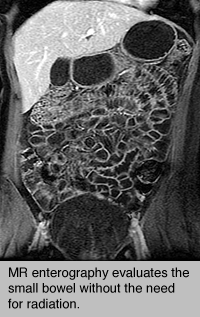

MR enterography evaluates small bowel without the need for radiation.An MR enterography procedure uses magnetic resonance imaging (MRI) technology to obtain detailed images of the small bowel.  MR enterography, also called Magnetic resonance enterography (MRE), is a complementary advanced, accurate and noninvasive diagnostic imaging test to evaluate a broad range of disorders including Crohn's Disease.